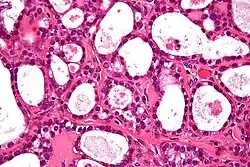

Ovarian clear-cell carcinoma often occurs as a pelvic mass that rarely appears bilaterally. The cells usually contain glycogen with large clear cytoplasm. It is also associated with endometriosis, a disorder of abnormal tissue growth outside of the uterus.[3] The tumor cells emerge in a stepwise manner from adenofibromas which are benign endometriotic cysts. They also hold molecular genetic mutations in both ARID1A and PIK3CA, similar to other epithelial ovarian cancers. Mutations in ARID1A commonly contain phosphatase and tensin homolog (PTEN) that are hypothesized to contribute to clear-cell tumorigenesis. However, research also shows that inactivation of ARID1A alone does not lead to tumor initiation. However, clear-cell tumors rarely carry p53, BRCA1, or BRCA2 mutations.[4] In addition, they also test negative for estrogen and progesterone receptors and Wilm tumor suppressor 1.[5] Studies have also suggested that clear-cell carcinoma can occur with thromboembolic complications and hypercalcemia. Recurrence of tumor cells have been reported to involve lymph nodes and parenchymal organs.